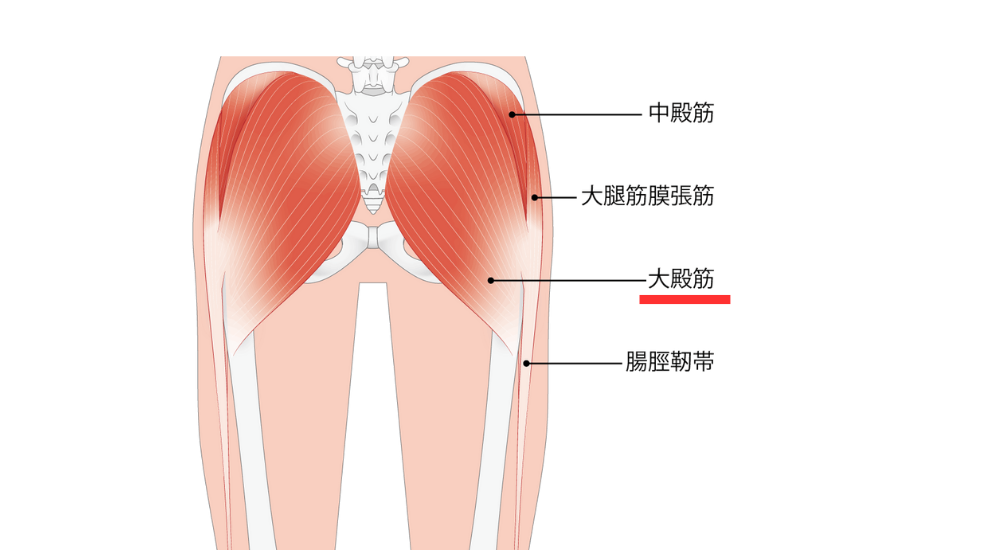

- 大臀筋・中臀筋・梨状筋:

お尻の筋肉。股関節の動きや骨盤の安定に重要で、機能低下や硬さが腰に影響することがある。梨状筋が硬くなると、坐骨神経を圧迫し、腰やお尻、足にかけての痛みを引き起こすことがあります。(梨状筋症候群)

なぜ、あなたの腰ばかりが疲れてしまうのでしょうか? それは、本来働くべきお腹のインナーマッスル(腹横筋)や、お尻の筋肉(大殿筋)が“サボって”いるため、その仕事をすべて腰の筋肉が肩代わりしている「代償動作」が起きているからです。 私たちは、詳細な動作検査や筋力検査で、この「サボり筋」を正確に特定します。腰だけを施術するのではなく、お腹やお尻の筋肉が再び正しく使えるように働きかけることで、腰への過剰な負担を根本から解消します。